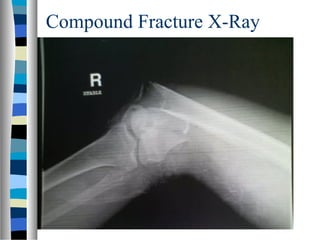

Compound Fracture X-Ray

Compound Fracture

 Also Called an Open Fracture

 Occurs When There is a Break in the Skin Around a Broken Bone.

 To Be Classified as Compound Fracture,

– Outside Air (and Dirt and Bacteria) Must Be Able to Get to the

Fracture Site Without a Barrier of Skin or Soft-Tissue.

– Therefore, Bone Does Not Need to be Through the Skin in Order

for the Injury to be Called a Compound Fracture.

The Fuss About Compound

Fractures

 Injuries Are Open to the Outside World

– There Is a Very Significant Risk of Developing an

Infection Around the Fracture.

– If Infection Develops, There Can Be Problems with

Healing Process

 Therefore, Compound Fractures Are

Generally Treated with Surgery to Clean the

Site of Injury and Stabilize the Fracture.